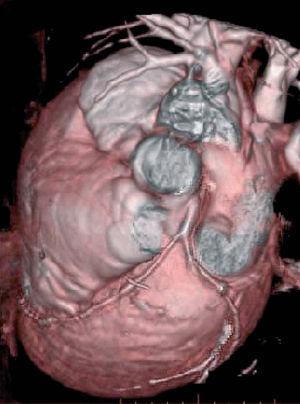

Se muestran las imágenes del árbol coronario que permiten descartar anomalías en esta localización. La figura 1 muestra una proyección axial de máxima intensidad (MIP) de la salida de las arterias coronarias. La figura 2 es una proyección coronal de máxima intensidad (MIP) de la arteria coronaria derecha similar a la proyección oblicua anterior derecha de la angiografía. Las figuras 3 y 4 son reconstrucciones en volume rendering en proyección oblicua anterior izquierda del tronco coronario izquierdo y su bifurcación y de la base del corazón, en la que se visualiza la salida del tronco coronario izquierdo. Se han retirado las venas pulmonares izquierdas. En la estación de trabajo, mediante el análisis avanzado de vasos se puede visualizar un vaso tortuoso o de trayecto curvo en un solo plano tomográfico permitiendo una cuantificación de la lesiones estenóticas. El estudio no detectó anomalía en la anatomía ni estenosis coronaria significativa en el paciente.

Figura 4. Reconstrucción en volume rendering de la base del corazón visualizándose la salida del tronco coronario izquierdo. Se han retirado las venas pulmonares izquierdas.